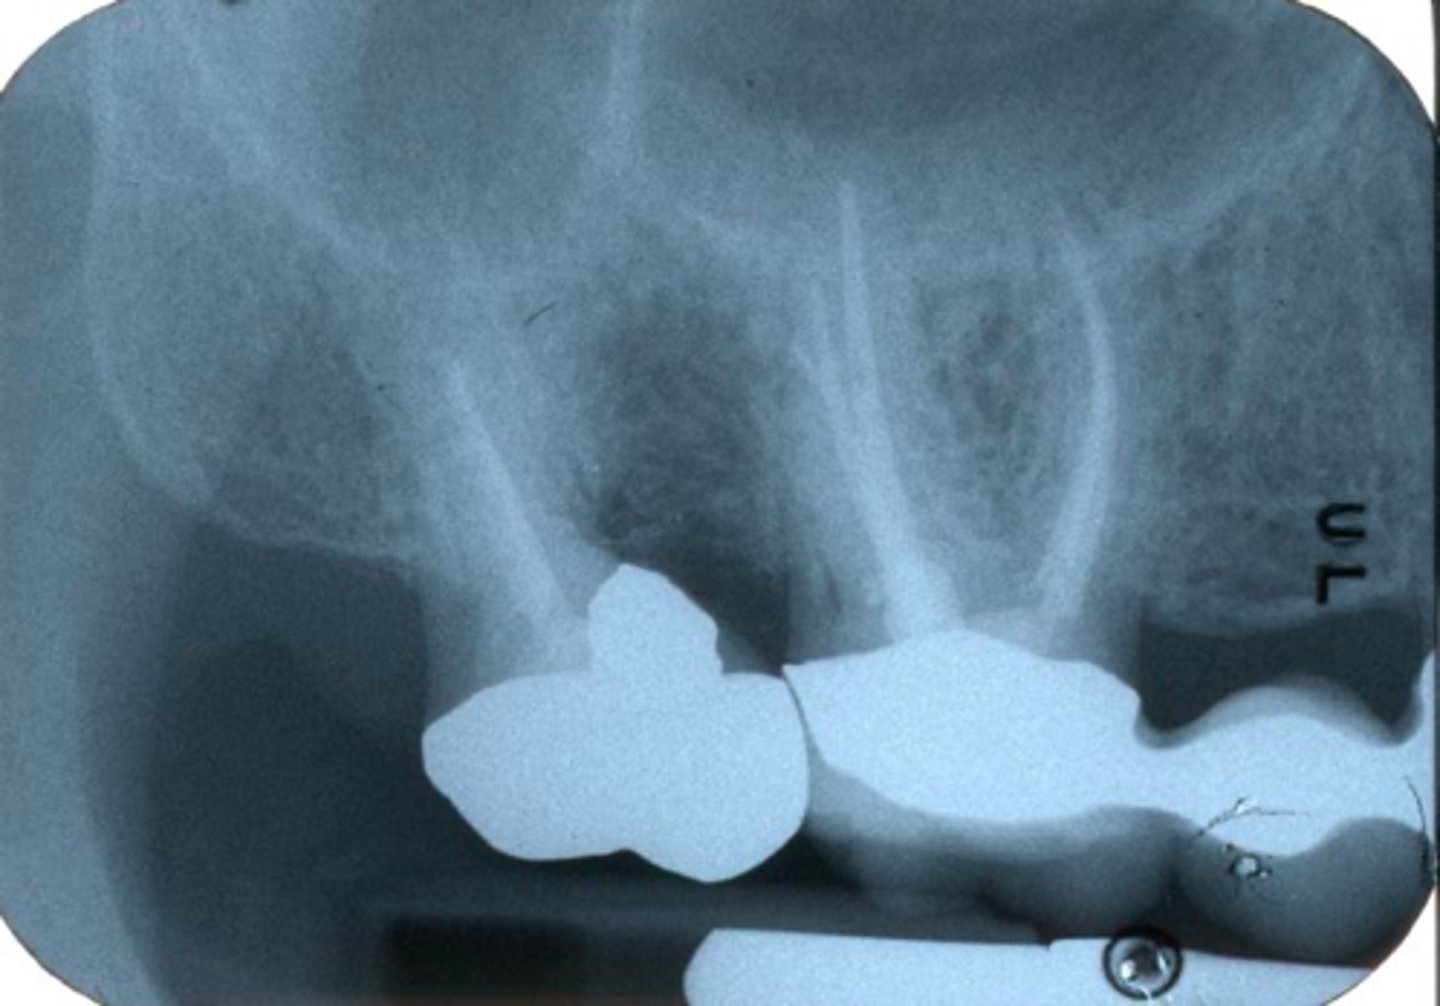

internal resorption

ID the indication for endo surgery:

(Communicated externally on the DB surface)

Invasive Cervical Root Resorption (ICRR)

What treatment is indicated?